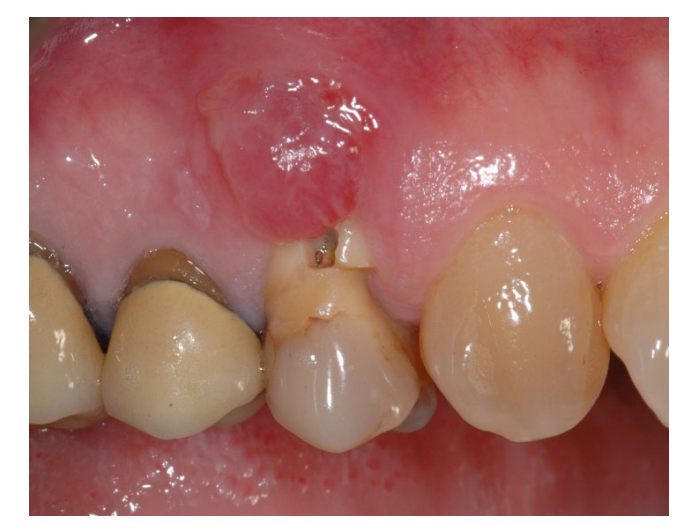

In group A, socket preservation with intentionally exposed non-resorbable d-PTFE membrane (test group, Figures 1–4), the residual alveolar socket was grafted with porcine-derived cancellous anorganic bone material (0.25–1 mm particles, Zcore, DeOre s.r.l., Negrar [Vr], Italy). Then, a non-resorbable, dense-polytetrafluoroethylene (d-PTFE) membrane (Cytoplast TXT1224, DeOre) was shaped according to the dimension of the residual socket, and it was inserted into a buccal and lingual pocket. Finally, a horizontal mattress suture (Cytoplast PTFE Suture 4-0, DeOre) was placed to secure the membrane and stabilize it to the soft tissue margins. The application of the non-resorbable d-PTFE membrane did not require primary closure via buccal flap advancement. The sutures were removed between 10 and 14 days post-surgery, and the non-resorbable d-PTFE membrane was removed between the fourth and the fifth weeks after surgery. After that, the wound was left to heal for about five months, allowing by the process of re-epithelialization.